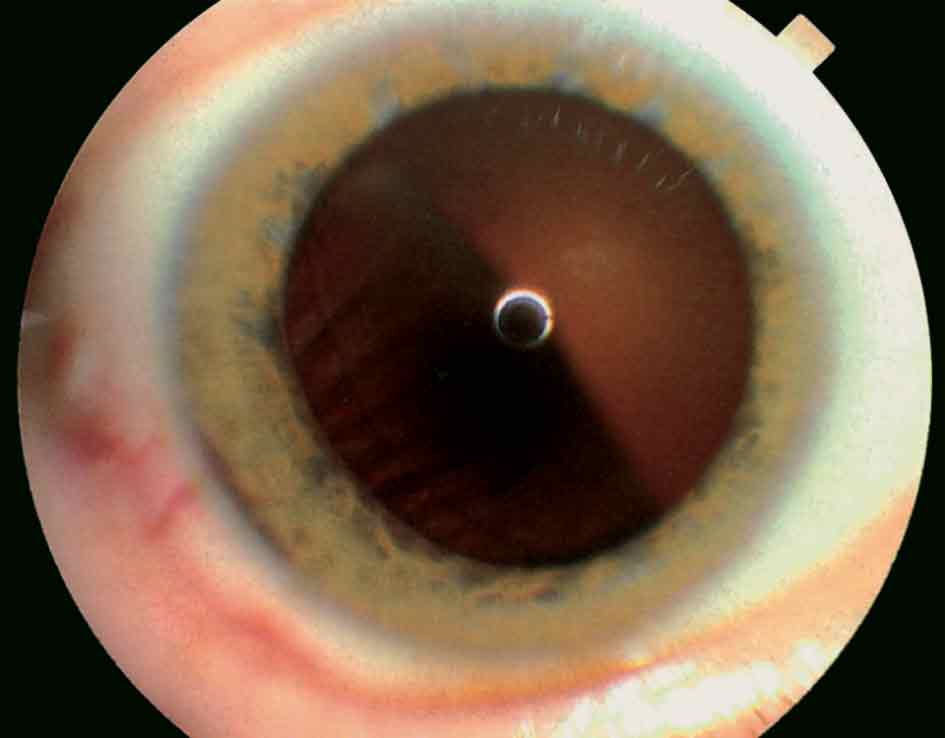

يؤلف ورم القزحية الميلانيني الخبيث 3% من الأورام الميلانينية الخبيثة في العنبة. وتشيع الإصابة به في العقدين الخامس والسادس من العمر. ويبدو غالباً بالشكل عقيدة وحيدة قاتمة اللون على الأرجح - وهناك عدد قليل من هذه الأورام بلا صباغ - (الشكل 5). وقد يجتاح الورم زاوية الغرفة الأمامية مع اختلاف صريح في اللون القزحي وزرق ثانوي. وتشمل التظاهرات السريرية الأخرى لورم القزحية الخبيث وجود شتر حدقي، وتشوه الحدقة، وساداً مقطعياً، وتوعية حديثة واضحة على سطح الورم.

الشكل (5): ورم قزحي ميلانيني خبيث.